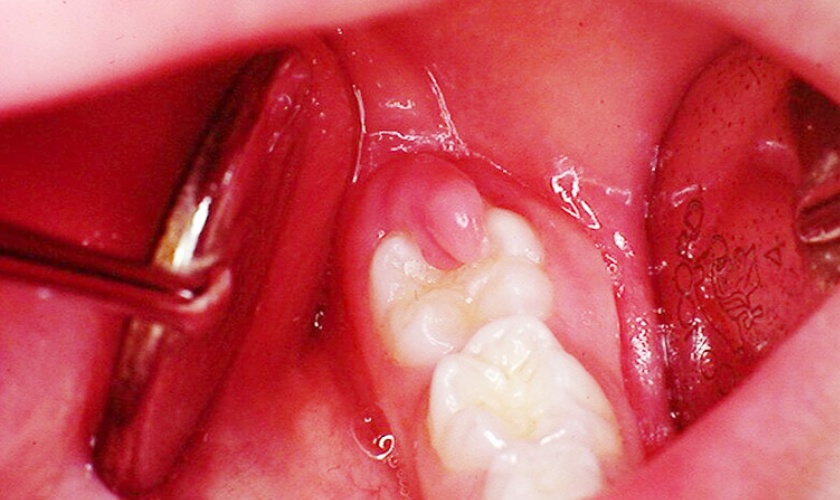

- Cắt lợi trùm răng khôn: Với trường hợp sưng lợi do răng khôn mọc thẳng nhưng bị lợi trùm, bác sĩ sẽ thực hiện cắt bỏ lợi trùm để răng mọc bình thường.